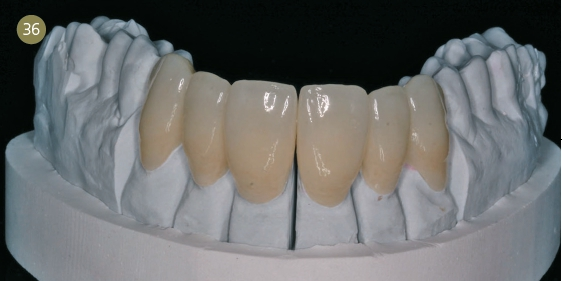

Die Veneerschalen wurden virtuell konstruiert (Abb. 5) und nach dem Nesten (Abb. 6) aus ultratransparentem dima HTE-Material in einer Wandstärke von 0,4 mm gefräst. Für das CAM steht uns unsere Cara DS mill 3.5 zur Verfügung (Kulzer). Die noch nicht gesinterten Zirkoniumdioxidkäppchen arbeiteten wir nach dem Heraustrennen nur noch mit einem speziellen Hochleistungsbohrer aus.

Jetzt wurden die Veneers unter morphologischen Kriterien ausgearbeitet und angepasst, bis ich die gewünschte Oberflächentextur erarbeitet hatte. Ich strebte zum Abschluss nur noch einen Malfarbenbrand an, ohne eine Glasurmasse zu benutzen.

Nach dem Abkühlen wurde die Keramikoberfläche dann per Hand noch einmal individuell poliert und der Glanzgrad eingestellt.